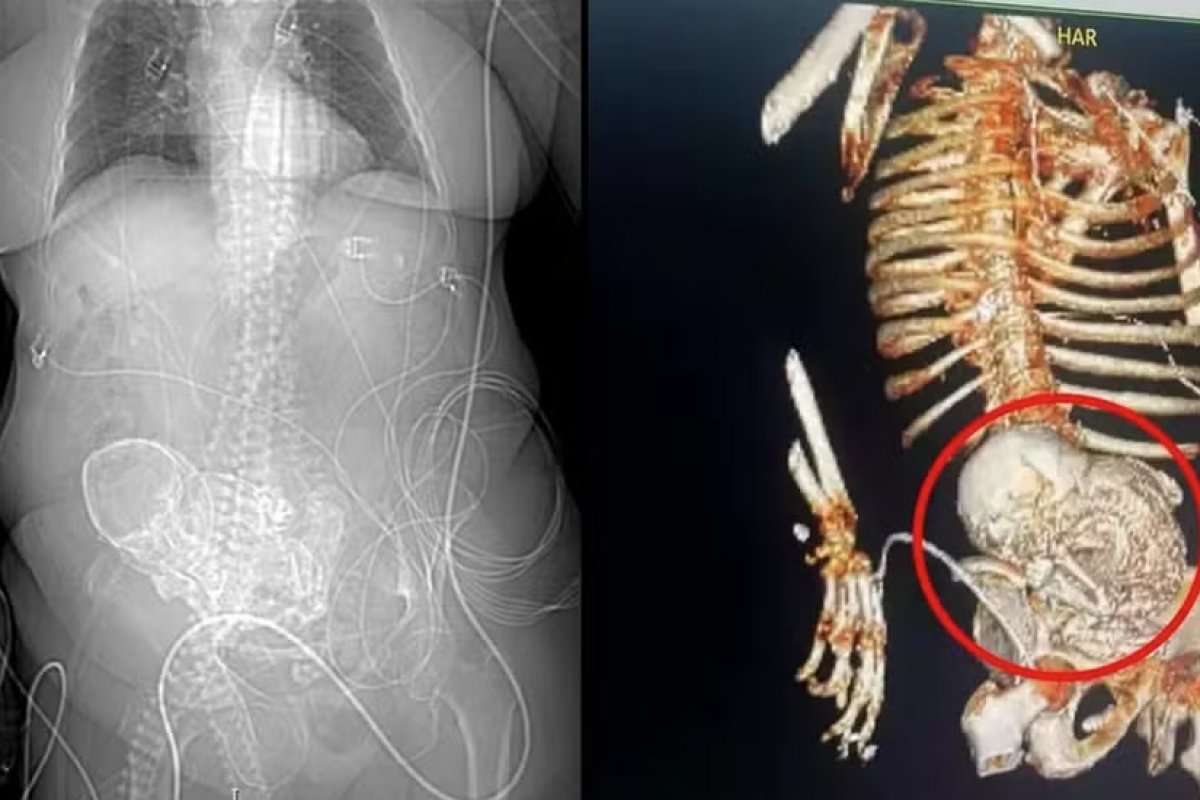

Uma idosa de 81 anos descobriu que carregava um "bebê de pedra" ao ser encaminhada para um hospital na região sul do Mato Grosso do Sul, com dores abdominais, de acordo com as informações do secretário de saúde da cidade, Patrick Derzi.

Segundo a equipe médica, a suspeita é de que a mulher estivesse com o feto calcificado no abdômen havia 56 anos, desde quando teve a última gestação. A idosa morreu logo após a cirurgia para retirada do feto.

A mulher deu entrada no Hospital Regional de Ponta Porã com um quadro de infecção grave em 14 de março deste ano. No mesmo dia, uma tomografia constatou o feto calcificado na região do abdômen da idosa.